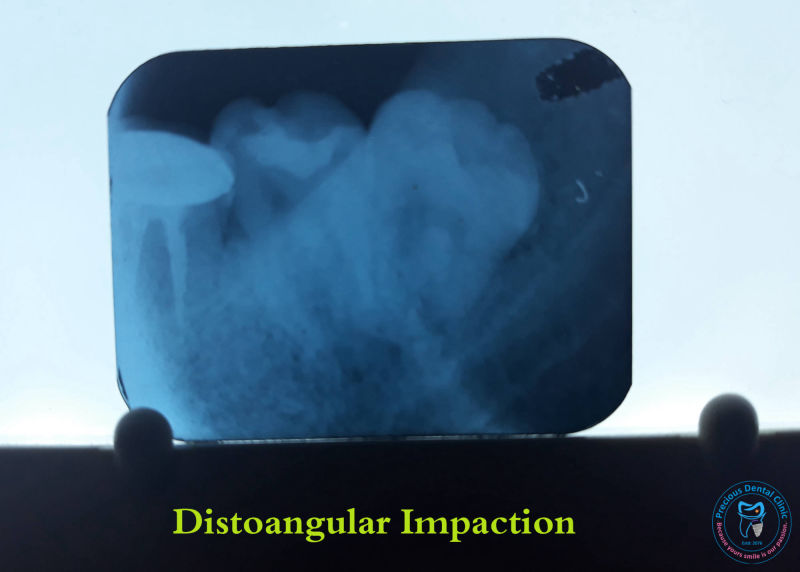

Dental Stomattis Distoangular impaction

Distoangular impaction Dog Bite